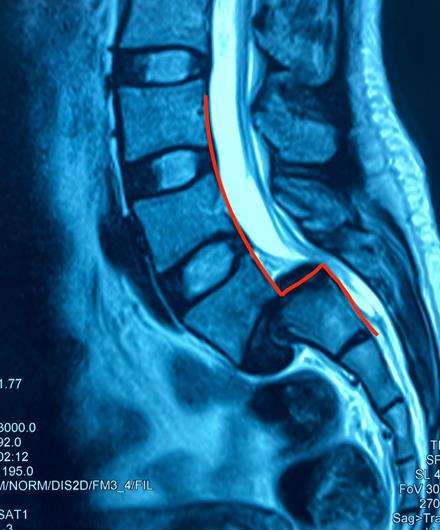

Đốt sống L5 bị trượt ra trước độ 4 trên phim MRI

Kết quả chụp MRI và X-quang cột sống thắt lưng tại Bệnh viện Hoàn Mỹ ITO Đồng Nai cho thấy, chị R. bị trượt thân sống L5 ra trước độ 4. Nếu không khẩn trương phẫu thuật có thể gây ra những biến chứng nguy hiểm như: yếu liệt hai bàn chân, thậm chí rối loạn tiểu tiện.